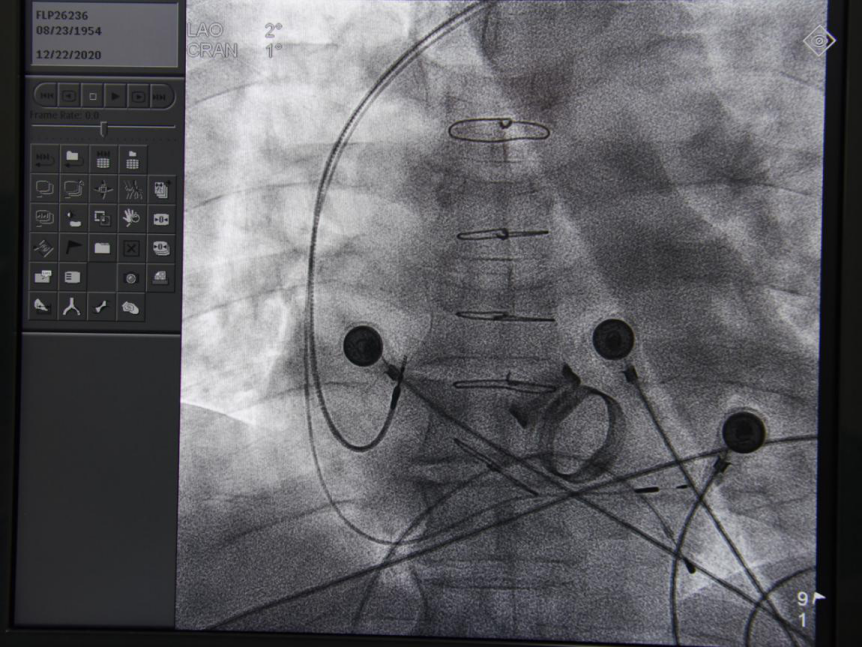

手术中

永久性心脏起搏器是治疗各种原因引起心动过缓和传导功能障碍性疾病的主要方法,常用的心房心室起搏不可避免改变了心脏的收缩顺序,对心功能造成一定影响,尤其是心功能不全的患者影响更大,希氏束起搏是使特制的3830电极导线通过特殊形状鞘送入右心室室间隔面,在心内电生理图的定位下旋入到左束起搏,起搏时心电向量与自身心律相同,QRS波无增宽,Vp-Ⅴ间期等于H-V间期,心肌收缩的顺序更接近正常心肌顺序,能更好地保护心功能。而希氏束起搏相对于传统起搏器起搏,除了可以改善传统房室传导阻滞者心率,缓解头晕、晕厥等症状,还可以改善传导阻滞及缓慢型房颤伴心功能不全患者心功能情况;目前大量循证依据提示希氏束起搏患者心脏射血分数与昂贵的心脏同步化治疗(CRT/CRTD)相仿,可做CRT双心室起搏的替代方案,同时减少医疗费用。